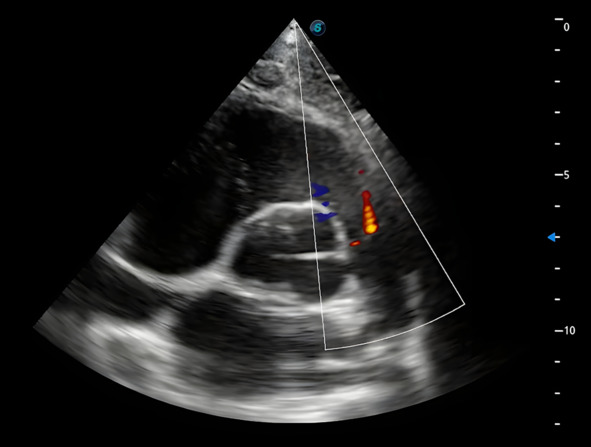

В этой позиции можно оценить, нет ли регургитации на пульмональном клапане, для этого нужно включить допплер и оценить изображение. Учитывайте, что незначительная регургитация на пульмональном клапане допустима, на рис. 8 представлен как раз такой случай.

Рис. 8